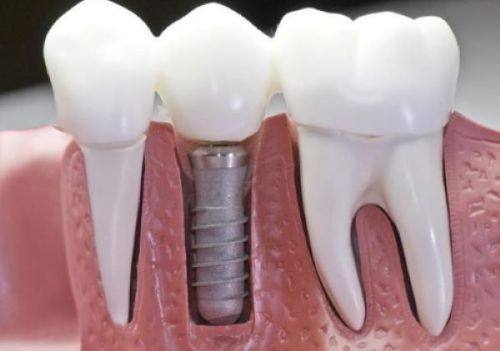

种牙打桩后,拆线时间主要取决于伤口的愈合情况。每个人的身体状况不同,伤口愈合速度也有差异。一般来说,种牙打桩后大概需要7天或者10天拆线。

如果患者自身身体素质较好,新陈代谢快,伤口愈合比较快,那么拆线时间会缩短,可能7天就可以拆线。相反,如果患者身体状况一般,或者在种牙后没有做好护理工作,导致伤口愈合比较慢,拆线时间就会延长,可能需要10天。